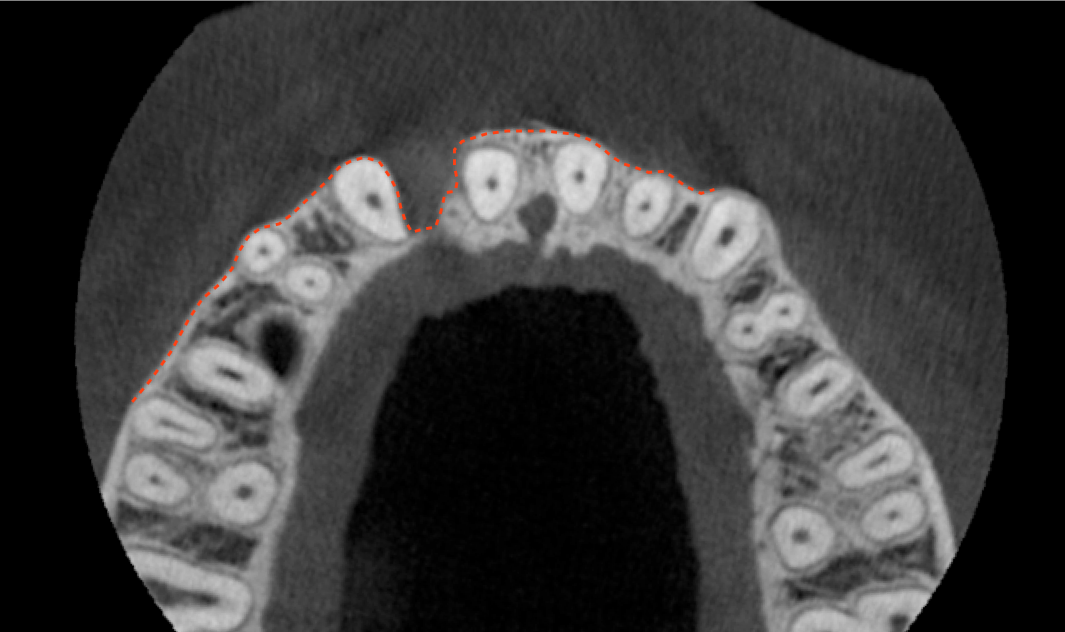

Tomographic images revealed a large tridimensional defect, with vertical and horizontal loss of bone extending to the apical third of teeth Nos. 6 and 8. Additionally, a buccal bone dehiscence was evident on tooth No. 5, and thin labial plates secondary to the orthodontic movement were present in several areas (Figure 3 and Figure 4).

After 3 months of post-orthodontic stabilization, a cone-beam computed tomography scan was taken to re-evaluate the results and plan the future treatment sequence. Tomographic images clearly showed vertical gains in alveolar height, including in the edentulous area corresponding to tooth No. 7 (Figure 10 through Figure 12). The apex of tooth No. 8 was forced-erupted beyond its socket and could be visibly located within the soft tissue.30,33